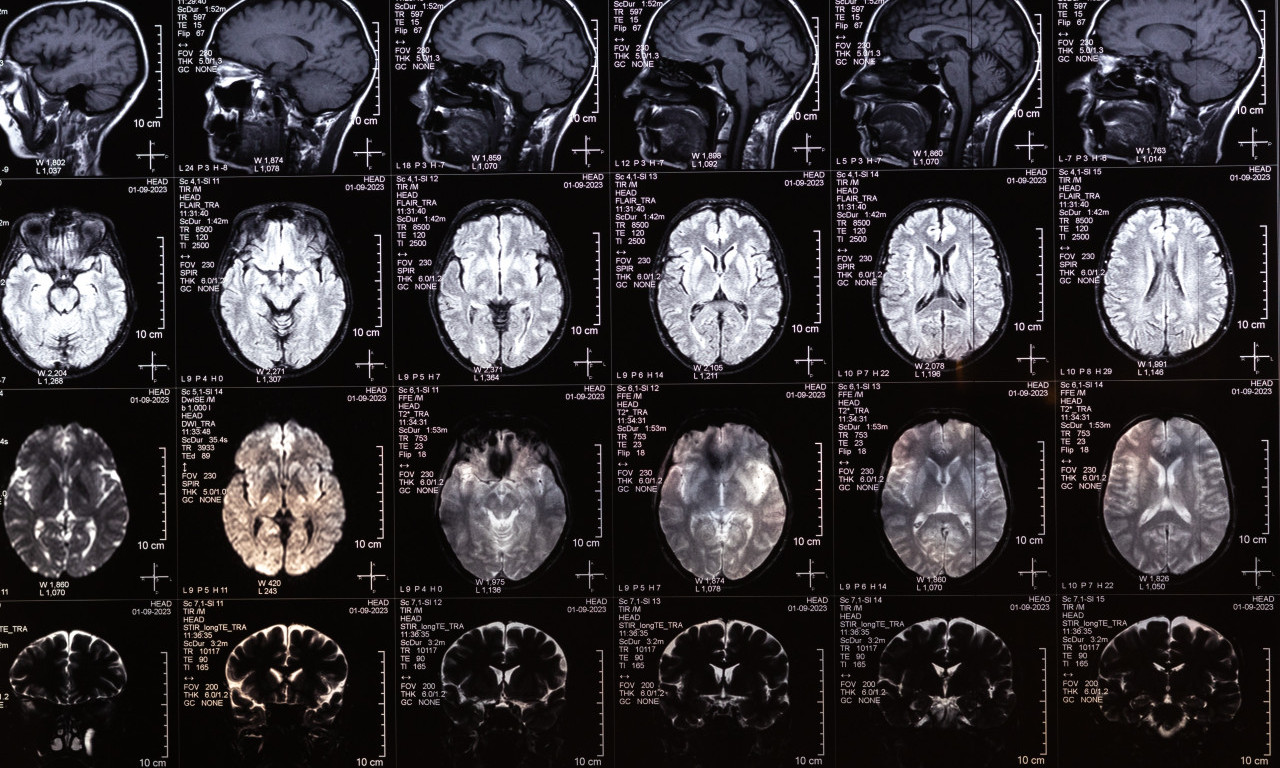

Istraživački tim sa Univerziteta Kembridž je analizirao 3.802 MRT snimka mozga i rekonstruisao obrasce neuronske povezanosti između rođenja i 90. godine. Podaci su otkrili iznenađujuće jasnu sliku: strukturna organizacija mozga ne odvija se kontinuirano, već u pet glavnih faza od kojih je svaka obeležena značajnim prekretnicama – oko 9. 32. 66. i 83. godine, piše Dojče vele.